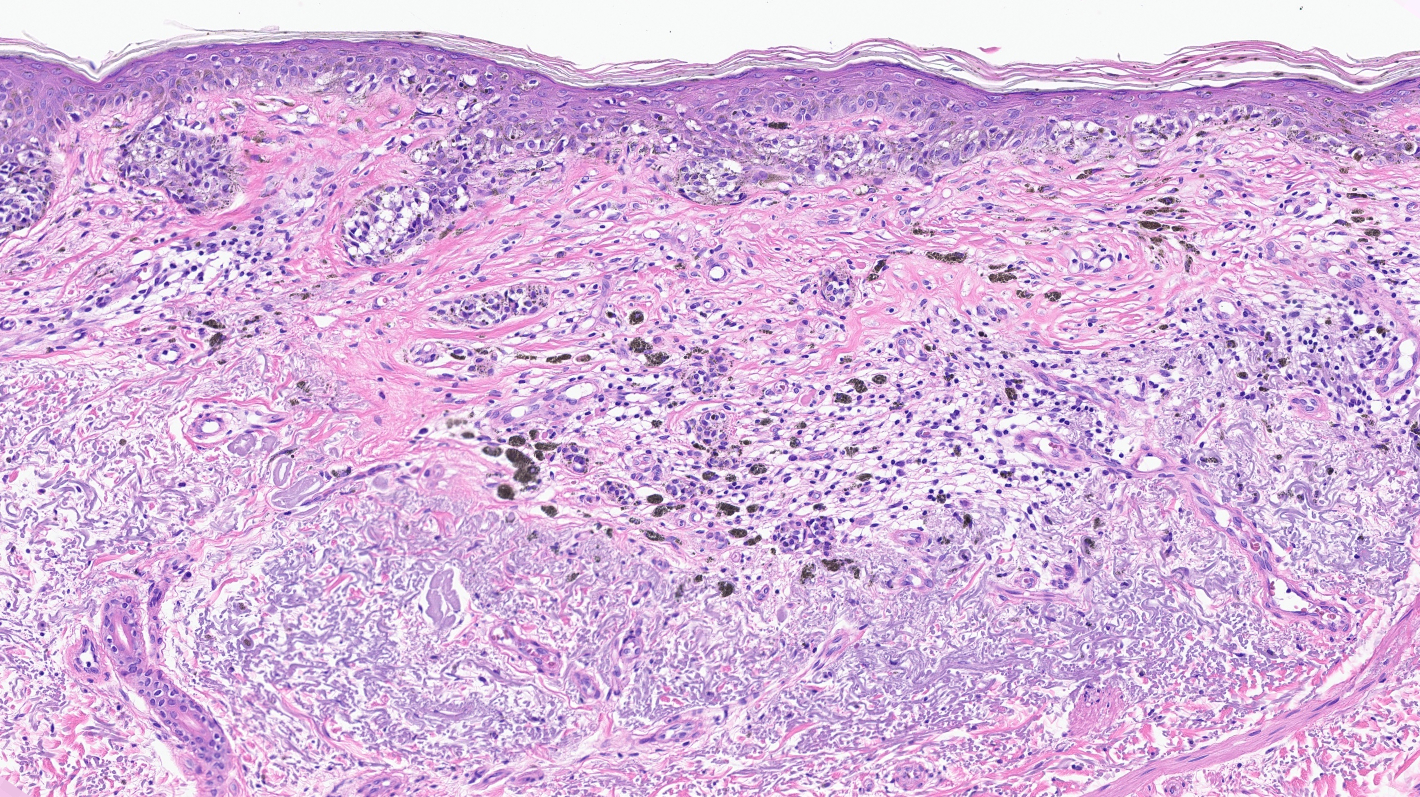

Microscopic (histologic) description

- Proliferation of intraepidermal (single and nested) melanocytes overlying solar elastosis

- Melanocytes demonstrate crowded growth along the basal epidermis

- Associated epidermal alterations, including loss (effacement) of epidermal rete and associated irregular epidermal hyperplasia

- Pagetoid scatter (melanocytes above the basal layer)

- Involvement of adnexal epithelium

- Melanocytic cytology is variable, ranging from small cells with dark nuclei and scant cytoplasm to epithelioid pigmented melanocytes, to spindled melanocytes

- Invasive component, if present, consists of single or nested melanocytes in the dermis with similar cytologic features to those in the in situ component (Cancer Res 1969;29:705, Am J Pathol 1969;55:39)

Microscopic (histologic) images

Contributed by Joseph Gillam, M.D., Jennifer Crimmins, M.D. and Mark Mochel, M.D.